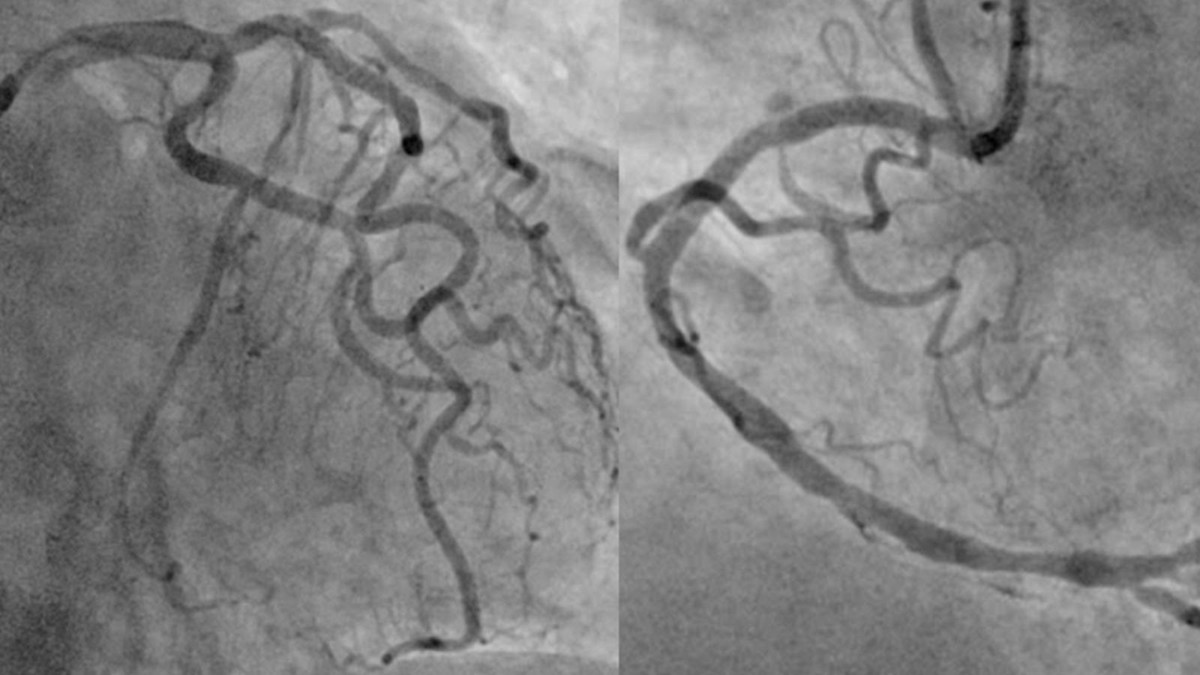

Hình ảnh mạch vành của người bệnh sau khi được can thiệp tái thông toàn bộ các động mạch vành tắc và hẹp. Ảnh BV

Sau khi giải thích kỹ chẩn đoán, định hướng điều trị, các lợi ích và nguy cơ của thủ thuật cho người nhà, người bệnh lần lượt được can thiệp nong bóng và đặt stent thành công cả ba nhánh động mạch mũ, động mạch liên thất trước và động mạch vành phải. Người bệnh sau đó được chuyển lên khoa Hồi sức tích cực – Chống độc để tiếp tục điều trị.